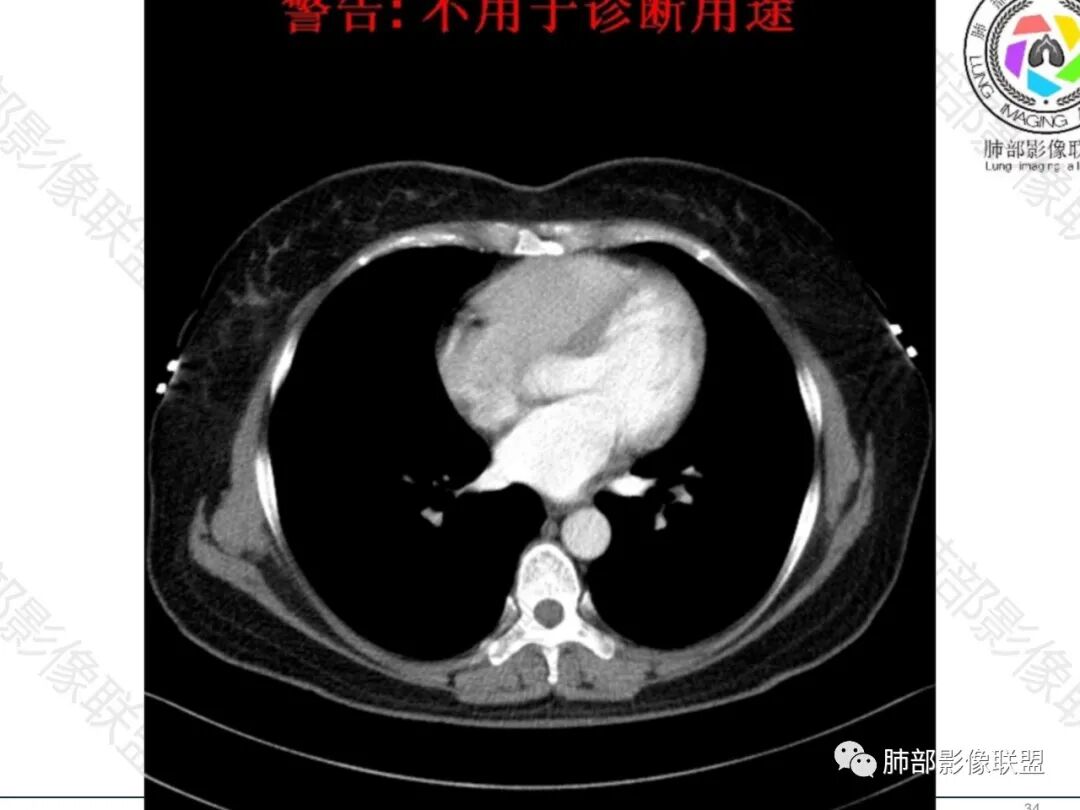

中年女性患者。左肺门上区, 围绕左肺动脉及支气管旁不规则形的病灶,支气管无变窄,肿块塑形增长,密度均匀,增强后边界比较清楚,肿块未见强化。临床提供给的病史价值不高,表现为轻咳,偶感乏力。影像学表现出偏温和的特点。考虑淋巴瘤。

左肺门淋巴结肿大,支气管呈针孔样狭窄,均匀强化,血管包埋漂浮,考虑小细胞癌,鉴别淋巴瘤。

女性,轻咳,左肺门区不规则软组织影,其内密度均匀,支气管受压变窄,未见截断堵塞,左主肺动脉干变细,增强轻度均匀强化,血管包饶,左主肺动脉及分支变窄,边界清晰,未见明显侵袭,常规考虑淋巴瘤,小细胞瘤待排,另右侧乳腺结节,纤维瘤?其他?建议其他检查。

中年女性,轻咳,乏力,影像表现:左肺门淋巴结肿大融合,血管无明显侵犯,支气管呈针孔样改变,远端支气管复出无异常,纵隔及主动脉旁多个稍大淋巴结显示,右乳结节。肺内小叶间隔增厚伴疑似小结节样改变。

这个左侧支气管在纵隔淋巴结内穿行时,明显变细变小了。

2.左肺门见多数增大淋巴结,跨叶分布,上叶支气管轻度狭窄,未见腔内结节或阻塞。

增大淋巴结密度不高,轻度均匀强化,有融合倾向,未见液化,压迫相邻肺动脉且与后者无间隙,左上肺动脉狭窄。

纵隔另见轻度增大淋巴结,梭形密度稍高,边界清楚。